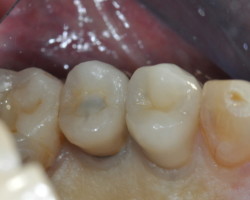

Avant-Après :